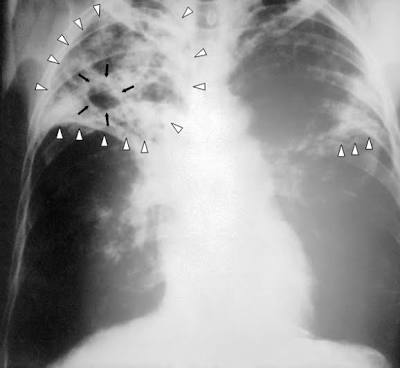

However, children who are not immunized against TB are likely to be infected from a TB positive patient because of their low immunity. Nevertheless, the symptoms is a little different from that of adultss. Tuberculosis should be suspected in children (0-14 years) with any or combination of symptoms such as low grade fever (which persists even when treated), night sweats, loss of weight, loss of appetite, failure to thrive, lymph node swellings, joint or bone swellings, angle deformity of the spine, restlessness, neck stiffness, headache and vomiting. Since coughing is not a likely symptons for children so as to collect their sputum sample for diagnosis, and since cases are often negative on culture, the diagnosis is always based on clinical findings, amily history of contact with a smear positive case, x-ray examination, and tuberculine test.